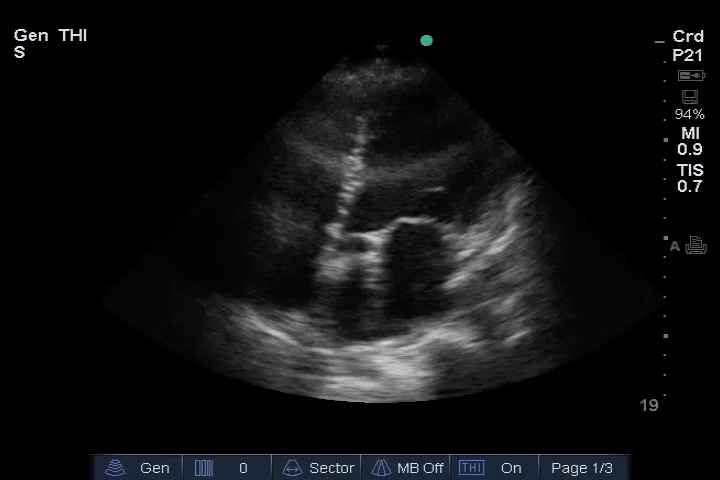

10_Heart_SC – LV reduced ejection fraction (EF)

11_Heart_A4CH – LV reduced ejection fraction (EF)